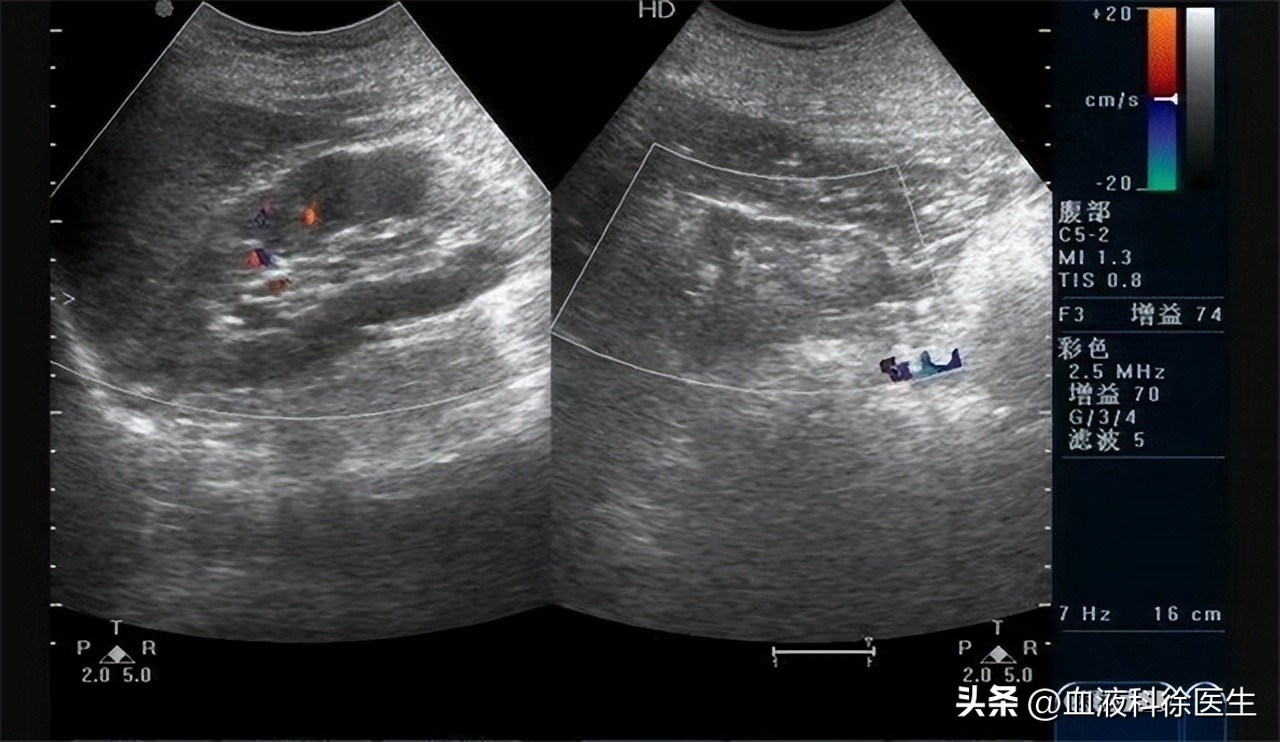

血常规检查结果显示尿素、尿酸、肌酐都有异常升高。尿常规检查结果显示红细胞、白细胞、尿蛋白量增加、尿液比重为1.012, 肾脏彩超看到肾脏出现萎缩,体积变小,皮髓质分界不清, 通过这些检查结果分析, 刘先生被确诊为肾衰竭 。